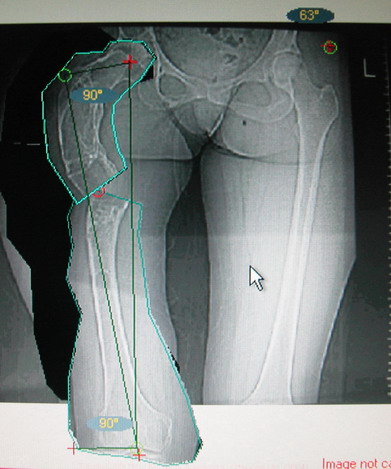

Возможна аппаратная коррекция оси с формированием клиновидного регенерата, которая решила бы и проблему укорочения (что, впрочем, нужно уточнить по схеме, сделанной по рентгенограмме с хорошим захватом смежных суставов - схемка по присланному снимку в приложении). По окончании коррекции - блокируемый стержень, который и сократит время пребывания в аппарате, и вообще возврата к нормальной жизни, а также будет мерой профилактики патологических переломов.

Собственно сустав не беспокоит, объем движений полный. По скиаграммам получается, что достаточно одной остеотомии на вершине деформации, чтобы восстановить длину и вывести коленный сустав в нужное положение.

Т.к. укорочение 7 см, то начинать будем с соеотомии и коррекции аппаратом. Спасибо